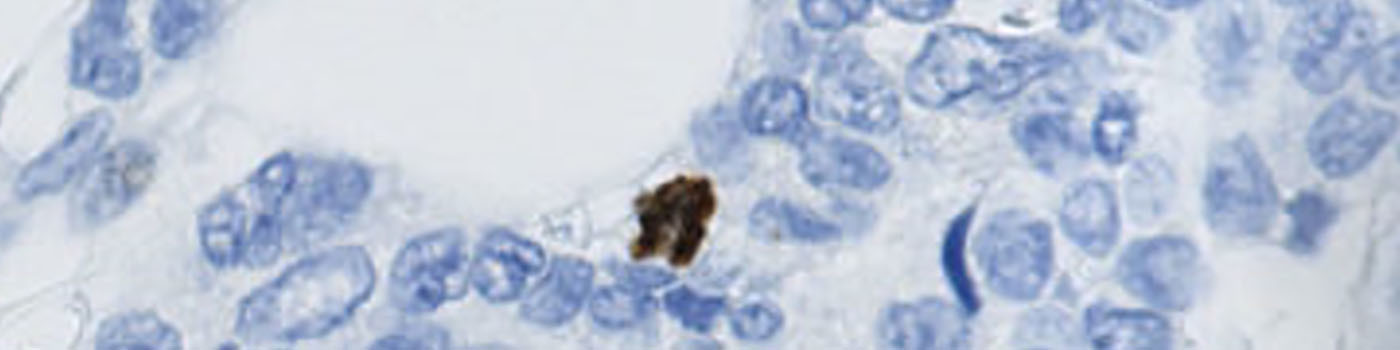

This APP has been developed to quantify the mitotic index of PHH3 positive cells within breast carcinoma. Phosphohistone H3 (PHH3) is a mitotic marker and has prognostic capabilities when applied to breast cancer tissue, see [3]. The mitotic index can be obtained by PHH3-immunohistochemical staining, which can be used as a supplement for diagnosis.

Tumor areas are manually outlined as regions of interest (ROIs) (see FIGURE 2). The ROIs are used for subsequent analysis limited to the inside of the tumor regions (see FIGURE 3).

Segmentation is performed of all nuclei (both PHH3 positive and negative). The method for nuclei separation which is based on shape, size and nuclei probability is used, employing a fully automated watershed-based nuclei segmentation technique. A post-processing step involving a morphological closing operation is applied to avoid counting nuclei in the late mitotic phase (anaphase and telophase) as two nuclei.

The number of positive PHH3 nuclei and the mitotic index is calculated.